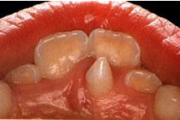

Suulaepoolt lõikunud koonilise kujuga lisahammas